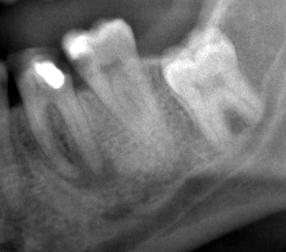

Конечно хотелось бы сохранить пульпу, но не знаю насколько это возможно. Про Пульпотек спрошу конечно. А как технически можно сохранить пульпу, если кариес подобрался уже очень близко? Снимок есть, под зубом вроде бы всё нормально. Вот снимок:

Восьмёрка ещё не вылезла, семёрку надо перепломбировать, а вот шестёрку лет 10 назад резорцином заполнили, теперь нужно коронку ставить со штифтом, как врач мне сказал.

перед тем как ставить коронку на 6 зуб,обязательно перелечите каналы , судя по снимку у вас там хронический периодонтит.

А по поводу семерки ,можно смело ставить постоянную пломбу- кариес до нерва не добрался

Технически - попытаться обработать кариозную полость не вскрыв пульпарную камеру, затем поставить лечебную прокладку (желательно Life, но подойдут и российские аналоги), на лечебную поставить изолирующую прокладку из компомера, затем уже саму пломбу.

Шестерку нужно будет полечить. Попросите Абсцессремеди. И главное чтобы он вышел за апекс. Сразу не протезируйтесь. Ждите, этот зуб уже никуда не торопится. Кстати, при надавливании на зуб больно?

Я бы не был столь оптимистичным. Между кариозной полостью и пульпарной камерой осталось небольшое растояние, которое может быть представлено размягченным дентином, при удалении котрого может обнажиться пульпа. В принципе и это не смертельно, потолще слой Лайфа, и временную пломбу на пару недель.

Я б депульпировал такую семёрку.

Шестёрку перелечивать надо. Судя по снимку, перелечить вполне реально. Если нет перфораций и если каналы хорошо отмыть хлоркой со звуком, то жить этому зубу ещё долго и счастливо. :)